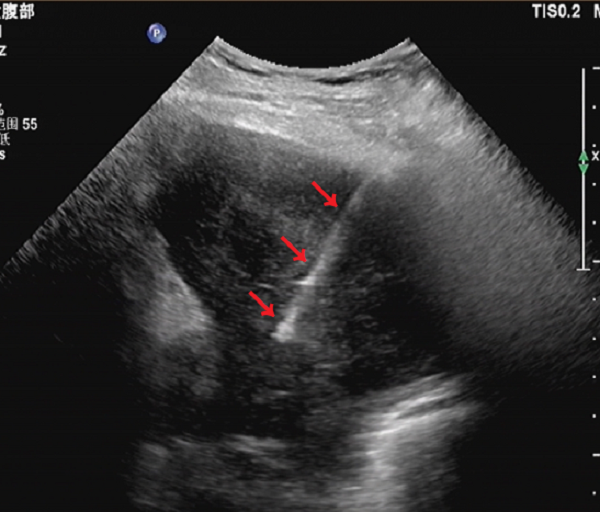

穿刺过程:患者平卧位,对左上肺中等回声超声引导下选择穿刺点,常规碘伏消毒后铺巾,以1%盐酸利多卡因局部麻醉至壁层胸膜,避开血管处,以18G穿刺针在彩超引导下穿刺病变部位(图2),取出组织3条(图3),送病理检查。

图2 红色箭头所指白色线条为进入肺部病变部位的穿刺针